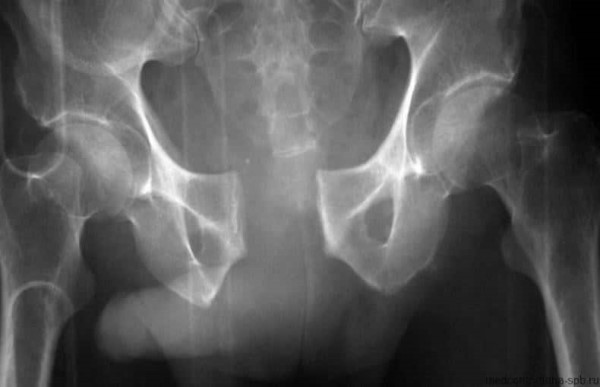

Хоть расхождение лобковых костей и считается нормой, есть степени их расширения.

| Расширение лобковых костей, мм | Описание |

| 4-5 | Это нормальный показатель. |

| 6-8 | Свидетельствует о 1-й фазе симфизита. Состояние не несет опасности для женщины или ребенка, но важно следить, чтобы лобковые кости не продолжили быстро расширяться. |

| 10-20 | 2-я стадия. Состояние довольно серьезное, требующее лечения. |

| 20 и более | 3-я стадия симфизита. Опасное состояние. |

Симфизит (симфизиопатия) – это отклонение опорно-двигательного аппарата, приводящее к болям. Одновременно с чрезмерным расширением лобковых костей могут наблюдаться не только боли. Самой большая опасность в возможности развития воспалительного процесса. Именно поэтому не стоит заниматься самодиагностикой. Для постановки точного диагноза и определения степени расширения лобковых костей, проводится УЗИ и другие процедуры.